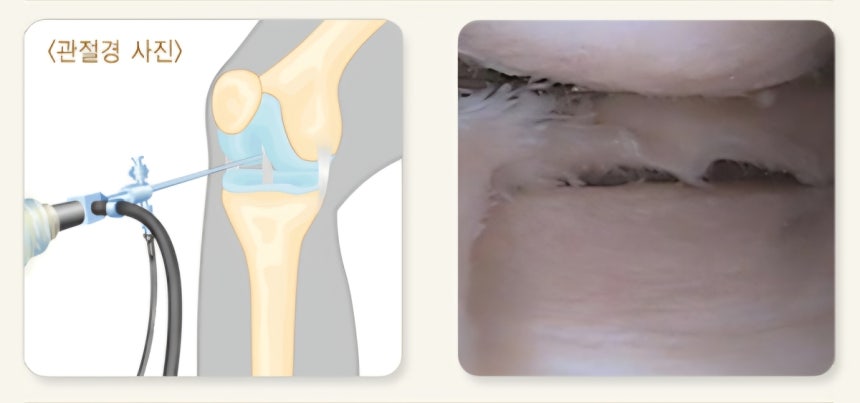

연구진은 치료 해법을 찾기 위해 필요에 따라 다양한 조직으로 분화할 수 있는 유도만능줄기세포에 주목했다.이 줄기세포를 연골세포로 분화시킨 뒤 아주 작은 공 형태의 3차원 조직으로 만들어 관절 안에 주사로 집어넣는‘MIUChon’치료제를 개발했다.흔히‘연골 스페로이드’라 불리는 이 세포치료제는 이전까지의 단순한 세포 주입 방식과 달리,무료 베팅 888 카지노연골 조직의 구조를 유지한 상태로 손상된 연골에 전달되도록 만들어졌다.

치료제의 효과 검증을 위해 쥐와 토끼를 비롯해 사람의 관절 구조와 유사한 개(비글)와 미니피그 같은 실험동물을 대상으로 실험을 진행했다.그 결과,손상된 연골 부위의 두께와 부피가 증가하고,무료 베팅 888 카지노연골이 닳아 생긴 결손 부위가 실제로 회복되는 양상이 확인됐다.보행 분석에서도 관절 기능이 개선된 것으로 나타났다.

특히 영상 검사와 조직 분석에선 주입된 인간 유래 연골세포가 관절 내 손상 부위에 실제로 정착해 새로운 연골 기질을 만들어내는 과정이 관찰됐다.작용 기전은 크게 두 가지 방식으로 나타났다.먼저 주입된 연골 스페로이드가 손상 부위에 직접 붙어 새로운 연골 조직을 형성하는 직접 재생 작용이 일어났다.이와 함께 연골세포가 성장인자와 항염증 신호 물질을 분비해 관절 안의 염증을 줄이고 연골이 다시 만들어지기 좋은 환경을 조성하는 간접 작용도 나타났다.연구진은 이에 대해 세포치료제가 일시적인 효과를 내는 데 그치지 않고 연골 재생에 직접적으로 관여할 수 있음을 보여주는 것이라고 설명했다.